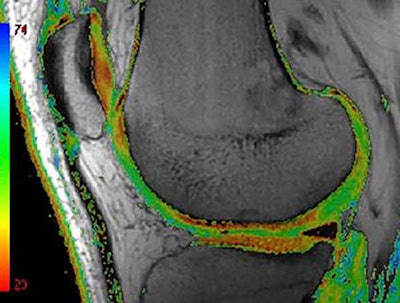

Compositional MRI can depict intratissue structural alterations that are not visible to the human eye. Color-coded T2 map MRI shows areas of focal increase in T2 times as green areas. T2 relaxometry is the most commonly applied compositional technique because it is available on most clinical MRI platforms. Image courtesy of Dr. Daichi Hayashi et al and BJR.Compositional MRI techniques, including T2 mapping or T2 relaxometry, can be used to look at the ultrastructure of tissue. Basically, the different analytical approaches are semiquantitative, quantitative, and qualitative compositional measures of tissue change, Roemer noted.